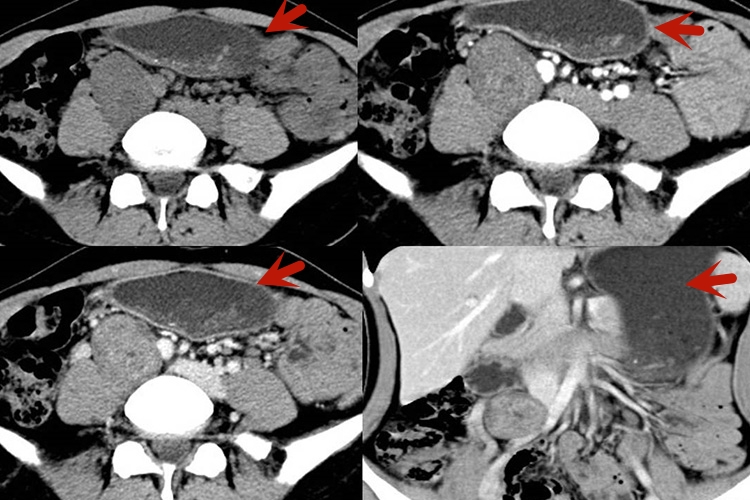

平滑肌肉瘤:平滑肌肉瘤多呈圆形、不规则形,大多有包膜而边界清楚,当存在周围侵犯时,可能表现为边界不清的肿块。